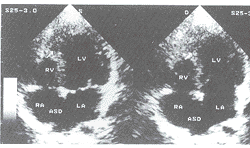

右心室发育不全合并继发孔房间隔缺损和肌部室间隔缺损1例

曾慧茹 侯传举 邓东安 孙培明 周晓丹 张玉威 曾慧茹(110003 沈阳市,沈阳军区202医院);侯传举 邓东安 张玉威(沈阳军区总医院)(沈阳军区总医院);孙培明 周晓丹(临江市林业医院) 中国超声医学杂志 2000 0 16 8